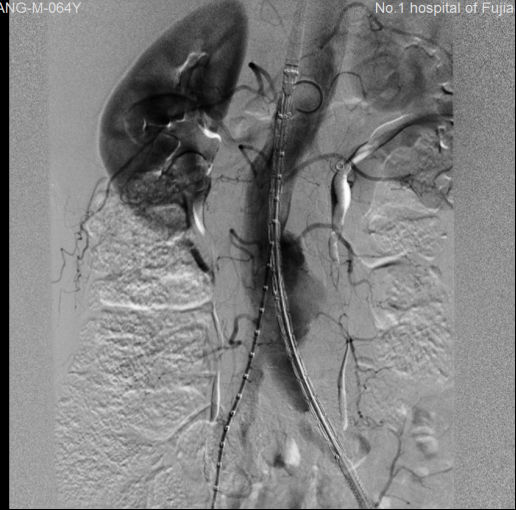

“行了!”,随着最后一枚支架的植入,郭平凡悬着的一个心终于落了下来,

介入手术室里的全体医务人员也都松了口气。造影确认,撤除导丝导管,缝合切口,安全护送病人回到重症室监护,患者生命征平稳,各项指标正常,又一例濒

临破裂的腹主动脉瘤在血管外科、急诊科、影像科、麻醉科、介入手术室等科室医务人员的通力配合下取得了成功。

术前 术后